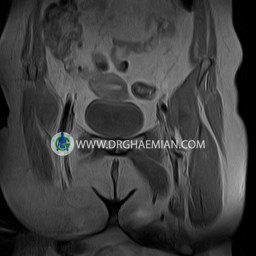

پزشکان اغلب از تصویربرداری ام آر آی برای تشخیص و درمان عارضه های پزشکی که فقط با استفاده از اشعه ایکس یا میدان مغناطیسی و امواج رادیویی قابل مشاهده است، استفاده می کنند. دستگاه ام آر آی تصاویر دقیق از ساختار های داخلی بدن ایجاد می کند. در این کیس کیست بارتولین لگن و تجمع دورمقعدی و کیست ساده ایی در تخمک چپی دیده می شود.

Technique : coronal STIR , coronal T2 , Axial T1 , axial T2 .

The femoral heads and acetabula are normal shape , signal intensity and the femoral heads are well covered by the acetabular margins .

The joint spaces are of normal width without fluid collection .

the articuler surfaces are smooth and congruent and show normal cortical thickness .

there are no marginal osteophytes or subchondral signal changes .

The bone marrow shows normal signal intensity , especially in the femoral head and neck .

– Simple cyst (28×32mm) in left ovary

– Cyst like lesion (20×25mm) in right vaginal wall suggestive for bartholin cyst and perianal collection

are seen.